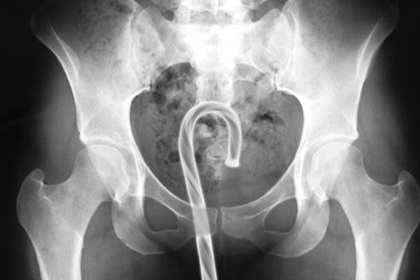

В гинекологической практике нередки случаи, когда женщины обращаются с жалобой на присутствие инородного тела во влагалище . Посторонние предметы попадают в интимные места как в детстве, так и в более взрослом возрасте во время сексуальных игр, при использовании . . .

Во влагалище половозрелых женщин посторонние предметы попадают при мастурбации, попытках предохранения от беременности или стремлении вызвать самопроизвольный аборт, а также, значительно реже, при проведении гинекологических манипуляций . Инородное тело . . .

В типичных случаях посторонний предмет может быть извлечен из влагалища пальцем, уретральными щипцами, пинцетом или зажимом с длинными узкими брашнами, ложкой Фолькмана . При попадании во влагалище гладких, круглых предметов (шариков, бусин, пуговиц и др .